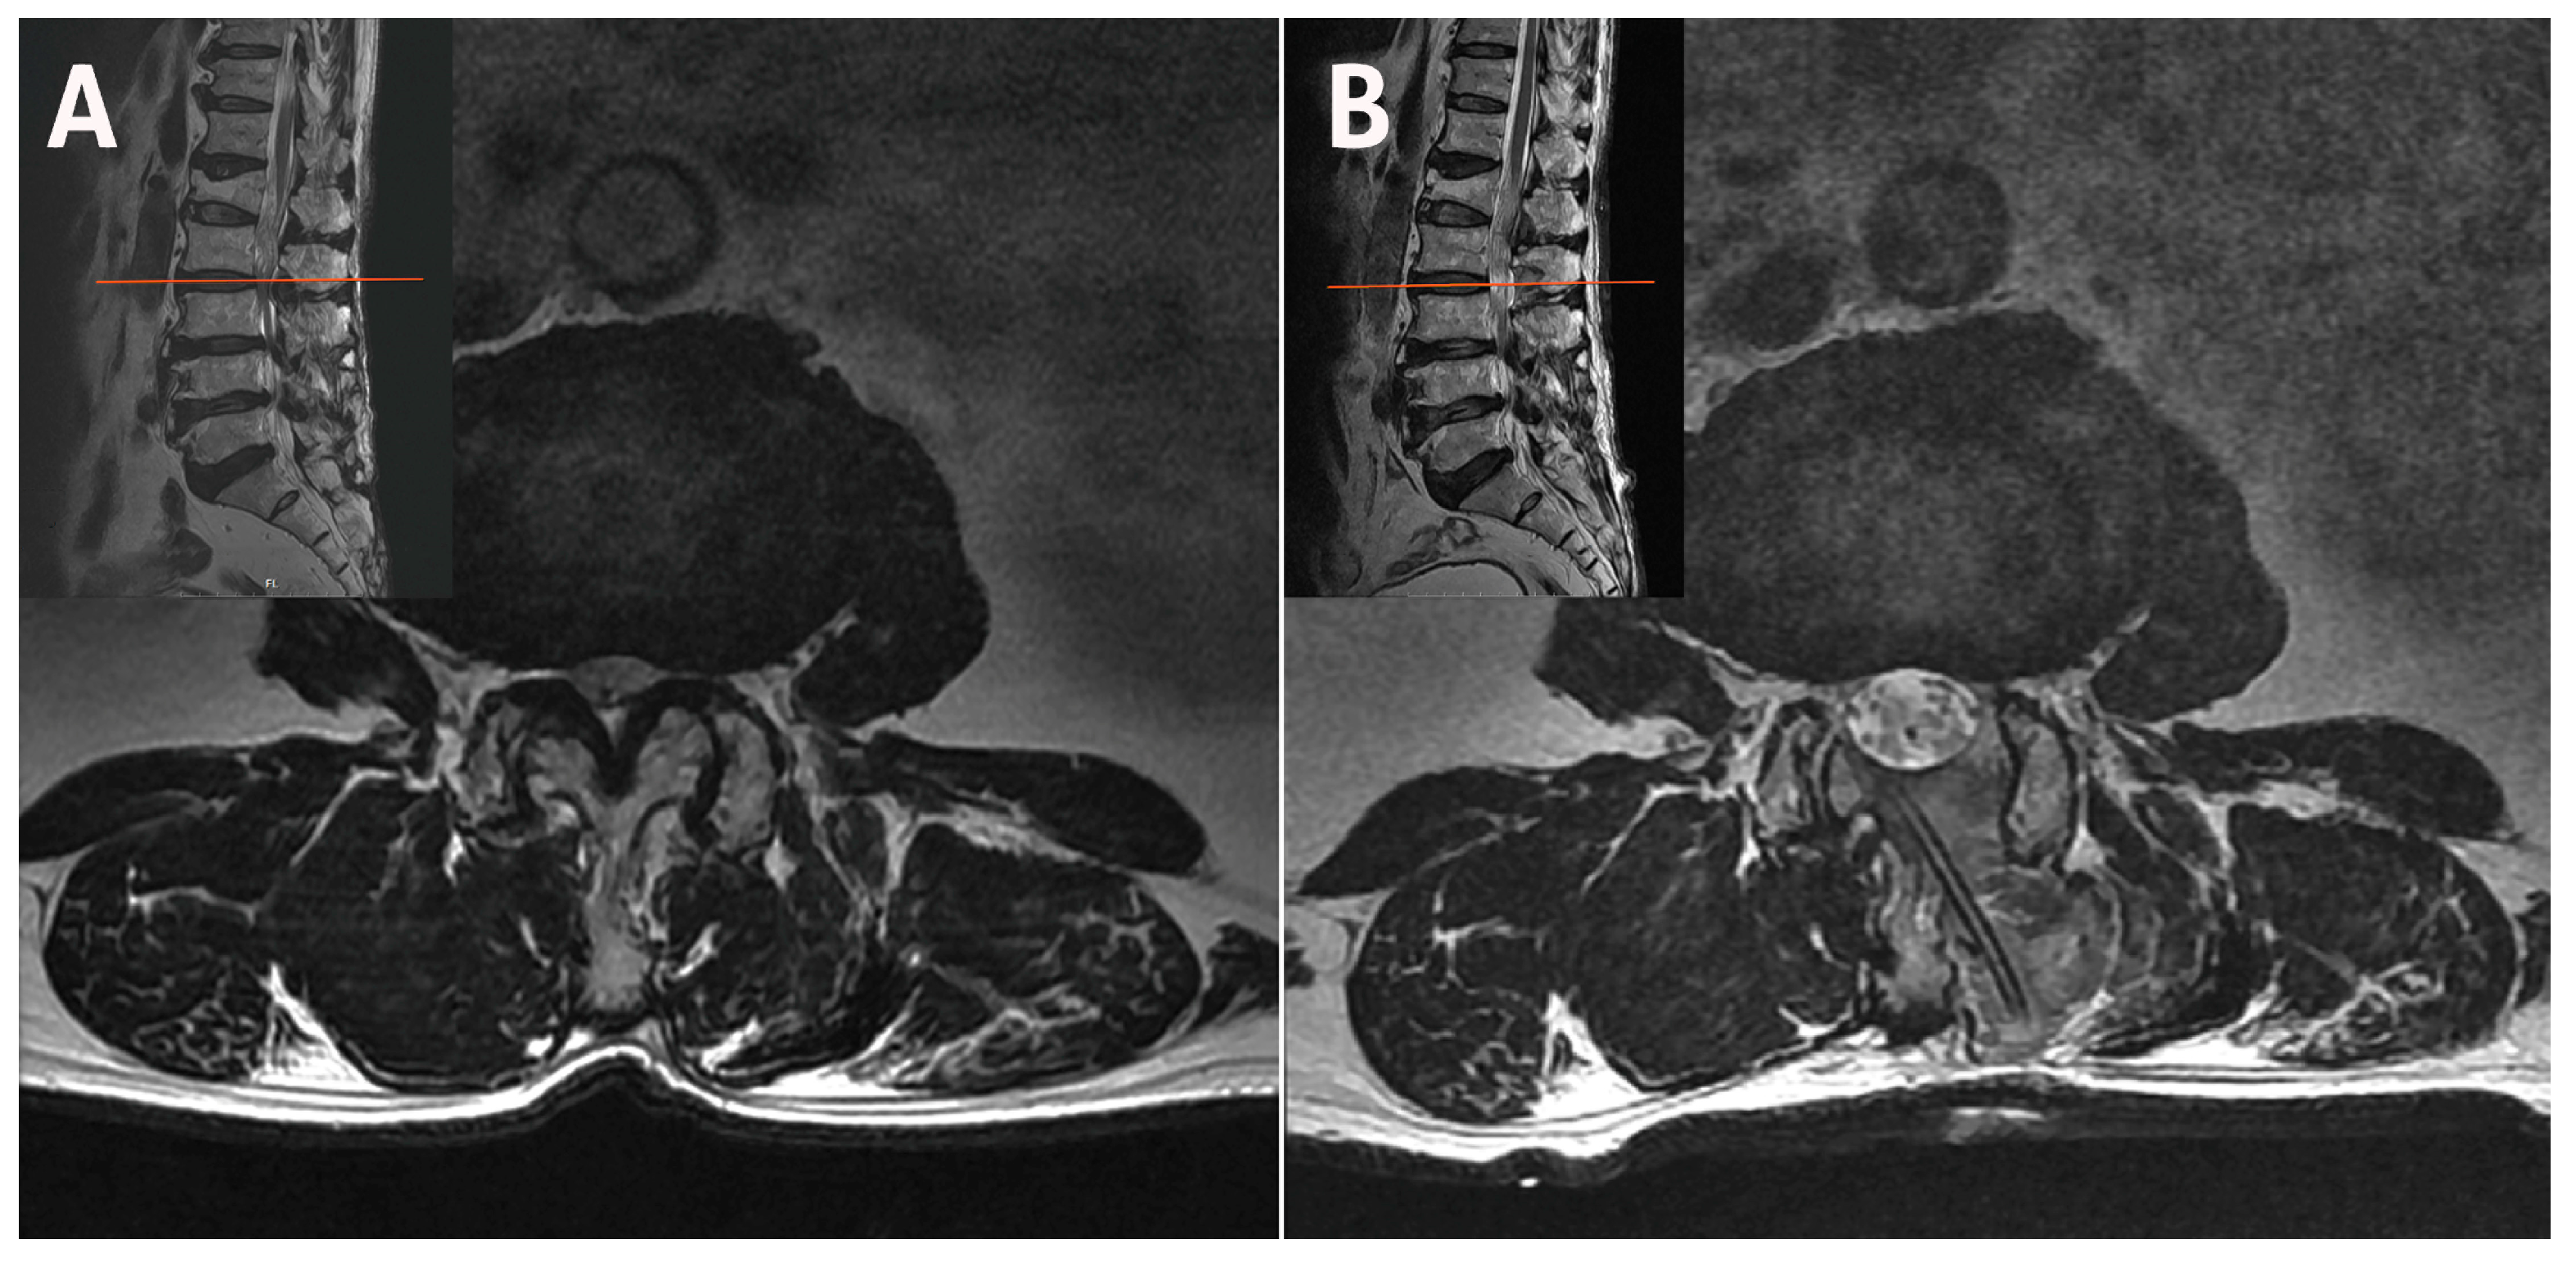

2.1. Case 1: Bilateral–Contralateral Decompression in Upper Lumbar Stenosis